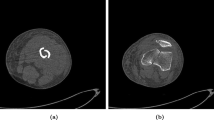

The segmentation of bone tissue from CT images is a complex process. It is difficult to find a solution that works in all cases. In a bone, there are two very distinct zones: cortical and trabecular tissue. Cortical tissue is very dense and it can be found in the outer part of the bone. Trabecular tissue is mainly in the inner part of the bone. This type of tissue is more heterogeneous and it has less intensity in a CT image. In addition, the intensity value for the same tissue differs between slices. This happens with both cortical and trabecular tissues. For instance, intensity values on the diaphysis and the epiphysis are different in a long bone (Fig. 1). Near the joints, the cortical zone is very thin. This zone even disappears in the area closest to the join. Therefore, the transition of the intensity values near the joints generally appears to be fuzzy and some areas within the bone may have similar intensity than the soft tissue surrounding the bone. This may cause incomplete segmentation or overgrowing [14].

Fractured bone tissue is more difficult to identify because it has some additional features to be considered. Due to the fact that bone fragments may have arbitrary shape and can belong to any bone in a nearby area, it is necessary to label all the fragments during the segmentation process. In some cases, this labelling requires expert knowledge. In addition, a priori knowledge can not be easily used because it is uncommon to find two identical fractures and therefore it is difficult to predict the shape of the bone fragments, specially in comminuted fractures. On the other hand, bone fragments are not completely surrounded by cortical tissue, since they have areas on the edges without cortical tissue due to the fracture. Finally, proximity between fragments and the resolution of the CT image may cause that different fragments appear together as one in the image. For this reason, smoothing filters should be used with caution. This type of filters can deform the shape of bone fragments and fracture zones or even remove small bone fragments. In some cases, it is necessary to detect the fracture zone of each fragment after its segmentation. The fracture zone is the area of the bone where the fracture occurs and is composed of trabecular tissue (Fig. 2). In situations in which bone fragments appear connected, it is difficult to accurately identify the fractured zone of each fragment. Therefore, post-processing can be necessary to delimit fracture zones in these situations.

There are several papers that are focused on the identification of fractured bone. With this aim, threshold-based methods are used in most cases. The most basic threshold-based method consist in defining an intensity interval that corresponds to bone tissue and calculating the pixels in the image that belong to this interval [24]. The intensity interval can be defined manually or can be calculated from the information provided by the image. On the other hand, the interval can be used in the hole stack or can be defined for each slice. The second option is usually the most successful because, as seen in Sect. 2, intensity values differ between slices. Several works propose to use thresholding to segment fractured bone. In [20], ulna, radius and carpus are segmented to simulate a virtual corrective osteotomy. Therefore, the segmentation is performed on non-fractured bones and then the segmented bones are virtually cut. In order to separate bone from other tissues, an user-defined threshold is used. In [27], the area where the bones are located is detected using a threshold-based method. Then, they present manual and semi-automatic tools for interactively segmenting bone fragments. This toolkit includes separation, merge and hole filling tools to generate individually segmented fragments from the result of the threshold-based segmentation. Thus, the method achieves accuracy at the expense of requiring a lot of user intervention. A global fixed threshold method has been utilized in [26] to detect the trabecular bone fracture zone. Due to the difference of intensity values between slices, it is difficult to set a threshold that fits all the slices.

Region growing is a threshold-based method that allows to limit the segmentation to a specific area [8]. To that end, the algorithm requires to place seeds before starting the segmentation. The selection of the seed points can be performed manually or automatically. The manual placement of the seeds enables the labelling of the different bone fragments. Moreover, the algorithm also needs to define an intensity interval. As in the previous case, the interval can be defined globally or for each slice. Once the seeds have been placed and the interval has been defined, the algorithm check all their neighbouring pixels. If the intensity of a neighbouring pixel is outside of the defined interval, it is discarded. Otherwise, the pixel is included in the segmented area and its adjacent pixels are studied. The algorithm stops when there are no pixels to study. The result of the algorithm can differ depending on the criteria used to accept or discard pixels. The basic algorithm accepts a pixel if its intensity is inside the interval. This approach allows to detect small bone features but image noise can also be segmented. However, noise can be mostly reduced using smoothing filters. Therefore, this approach can be suitable for segmenting fractured bone. Other approaches decide to accept or discard a pixel based on the intensity value of its neighbours. The simplest option is to accept a pixel if all its neighbours have intensity values inside the interval. Another option is to use a criteria based on statistical values calculated from the neighbouring pixels. In this case, small features could be discarded. Thus, this variation could not be suitable for segmenting fractured bone.

Region growing based methods are the best used for segmenting fractured bone. A semi-automatic threshold-based method and region growing have been utilized to extract bone contours from CT scans in [10]. Before that, thresholding is applied to obtain the area where bone tissue is located. Then, redundant contours are removed using an absolute and a relative spatial criterion. To improve the result, smoothing algorithms are applied and close contours are joined. In [11], authors use an interactive method to segment complex humeral bone fractures. In a first step, the method calculates a sheetness measure in order to extract the cortical layer of the fragments. Then, a semi-automatic region growing is performed on the obtained 3D sheetness data. Voxels with a sheetness measure less than a threshold are labeled as belonging to cortical bone fragments. Region growing is performed using a wave propagation strategy in order to reduce memory consumption and increase computation speed. Seed points and the sheetness threshold are interactively selected by the user. The placement of the seed is used to label the bone fragments, hence this process is repeated until all the fragments have been labelled. In [9], authors also use a sheetness-based method to segment fractured pelvic bones. In order to identify cortical tissue, a local adaptive thresholding method, based on the sheetness measure and a weight factor, is utilized. In order to segment trabecular tissue, a region growing method, based on the previous cortical bone segmentation, is applied using an adaptive threshold. In [14], authors present a multi-region segmentation approach to identify pelvic fractures. The seed points are automatically established by searching in the image pixels that have an intensity value higher than a threshold. Once a seed is found, its region is propagated to avoid finding another seed inside it. After that, a region growing algorithm propagates all regions in turns. In each cycle of propagation, the gray values of the fronts are set to be equal and reduced by the threshold iteratively. To that end, the threshold value is determined in an iterative process.